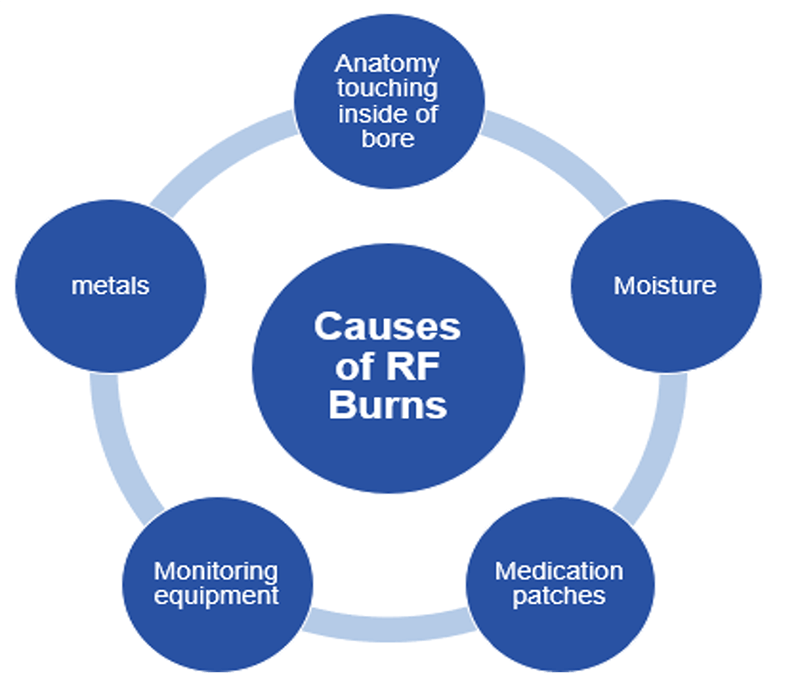

- Explain RF burns and provide examples of causes of burns

RF Burns

RF burns may result from the patient’s skin touching the sides of the bore inside the scanner. That connection of the tissue to the inside of the machine allows for direct transfer of heat. Moisture will also be a conductor. Sweat or moisture within the folds of the skin or even a damp diaper may provide just enough moisture to conduct a current and allow for a burn.

Many, but not all, medication patches have liquid within them and are designed to allow that liquid to flow from the patch to the skin, creating a moisture level on the skin as well. Hospital monitoring equipment touching the skin may also create a conducive situation. Oxygen monitors or a pulse-ox, have been known to cause burns, leads from EKG monitors or even IV tubing filled with liquid, IF touching the skin directly, may lead to RF burns. And of course, metals, which we have already discussed.

The dangers of RF burn, while rare, are very serious. Here we see a burn that was caused by a coil touching the patient’s skin. MRI burns are not always visible immediately. The skin may just feel warm to the touch at first. But MRI burns will worsen with time AFTER the scan has ended, and can get progressively worse over time without intervention.

The worst burns result in blistering of the skin, then peeling off the skin and sometimes scaring, similar to the results of getting a sunburn. There have been documented cases where patients require skin grafts after an MRI burn.

The best ways to prevent burns: Make sure there is a minimum of 10mm of padding between the patient’s skin and the inside of the bore. Make sure nothing that can act as a conductor is in direct contact with the patient’s skin. Lastly, make sure moisture is kept to a minimum on the patient’s skin during a scan.